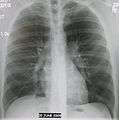

- Normal AP CXR

AP CXR showing left lower lobe pneumonia associated with a small left sided pleural effusion

AP CXR showing right lower lobe pneumonia

AP CXR showing pneumonia of the lingula of the left lung

Right upper lobe pneumonia as marked by the circle.- Left upper lobe pneumonia with a small pleural effusion.

- Right lower lobe pneumonia as seen on a lateral CXR